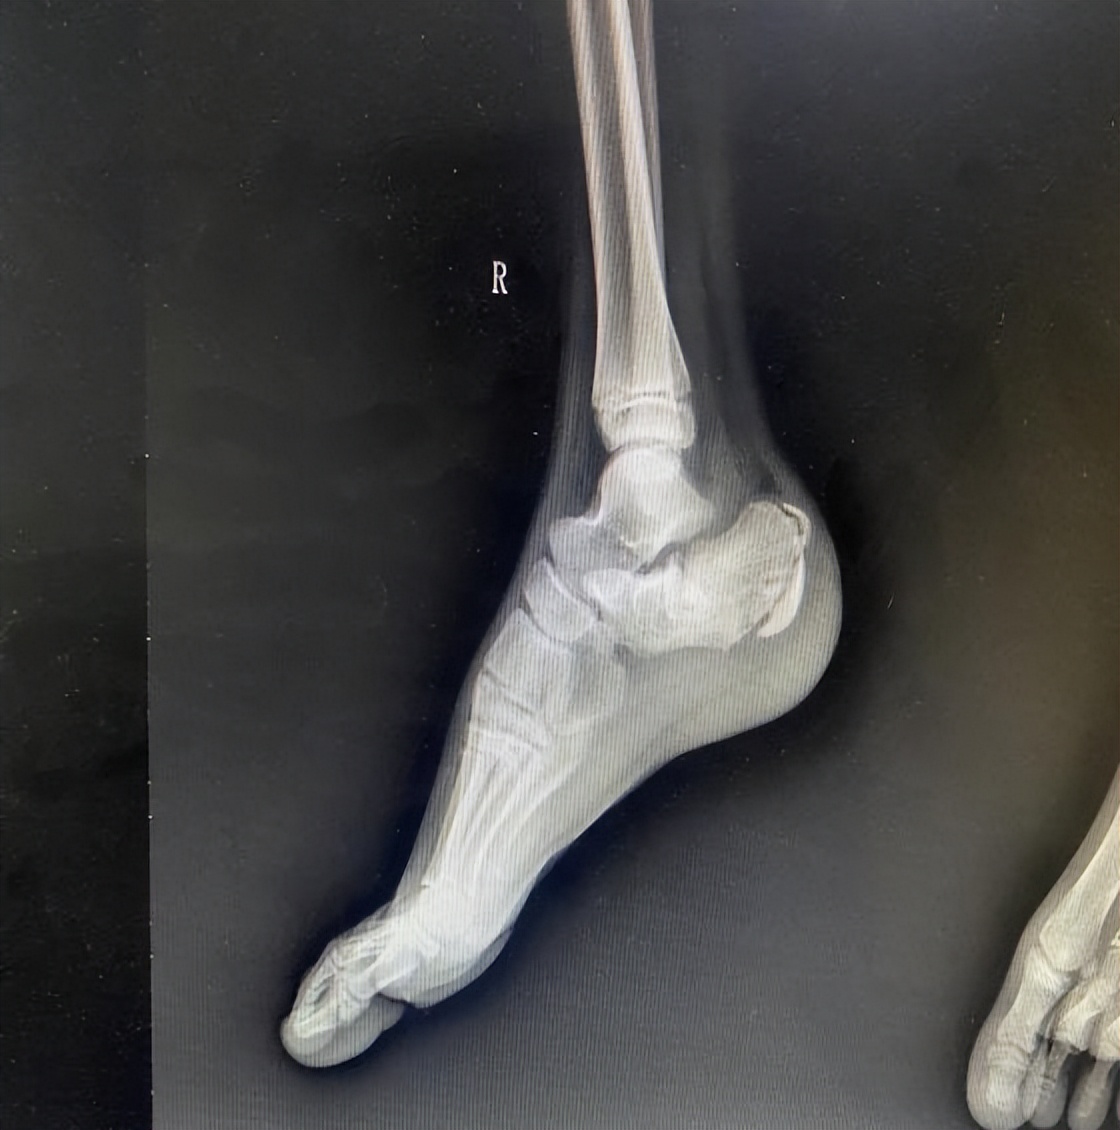

术前X线